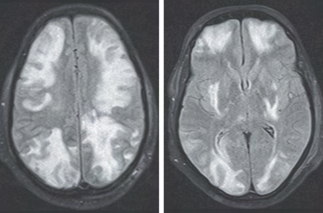

Recent studies indicate that Generative Pre-trained Transformer 4 with Vision (GPT-4V) outperforms human physicians in medical challenge tasks. However, these evaluations primarily focused on the accuracy of multi-choice questions alone. Our study extends the current scope by conducting a comprehensive analysis of GPT-4V's rationales of image comprehension, recall of medical knowledge, and step-by-step multimodal reasoning when solving New England Journal of Medicine (NEJM) Image Challenges - an imaging quiz designed to test the knowledge and diagnostic capabilities of medical professionals. Evaluation results confirmed that GPT-4V outperforms human physicians regarding multi-choice accuracy (88.0% vs. 77.0%, p=0.034). GPT-4V also performs well in cases where physicians incorrectly answer, with over 80% accuracy. However, we discovered that GPT-4V frequently presents flawed rationales in cases where it makes the correct final choices (27.3%), most prominent in image comprehension (21.6%). Regardless of GPT-4V's high accuracy in multi-choice questions, our findings emphasize the necessity for further in-depth evaluations of its rationales before integrating such models into clinical workflows.